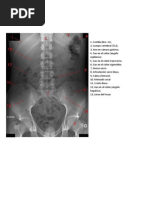

-Proyección básica: radiografía en decúbito supino

La radiografía de abdomen no requiere ningún tipo de preparación previa por parte

del paciente y suele realizarse en posición decúbito supino o en alguna otra

posición si el especialista así lo indica (Imagen 3). Para su realización será

necesario desnudarse y desprenderse de cualquier objeto que se puede tener,

especialmente joyas y objetos metálicos. La exposición a radiación ionizante por

parte del paciente como consecuencia de esta prueba diagnóstica, es leve y no

supone un riesgo importante para su salud.